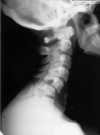

25

What is the most important finding out of these views?

Posterior translation of C1 | indicates a dens issue

26

Assuming this is due to trauma, what is the diagnosis? What is the most common mechanism? Is this condition stable?

Type 2 odontoid fracture Hyperextension Unstable | fracture through the base of the dens ## Footnote DDx: os odontoideum